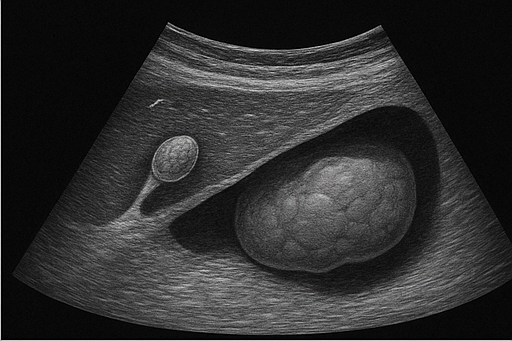

- 담낭 용종: 담낭 내부에 생긴 작은 돌출물로, 대부분 양성이지만 크기에 따라 추적 관찰이 필요합니다.

- 신장 종양: 신장에 발생하는 종양으로, 크기와 모양의 변화를 통해 의심할 수 있습니다.